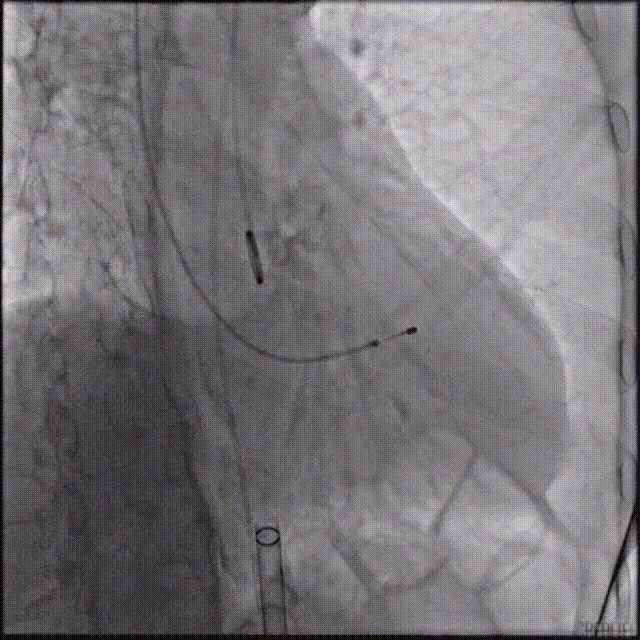

TaurusElite输送系统轻松过弓、跨瓣,AV23瓣膜瓣环上约2-4mm释放。

瓣膜初始位置释放

回收再定位释放

第一次释放到工作位后瓣膜下滑,回收调整位置后选择高位再次释放,最终造影显示瓣膜形态、位置良好,冠脉血流灌注正常,超声提示少量瓣周漏。